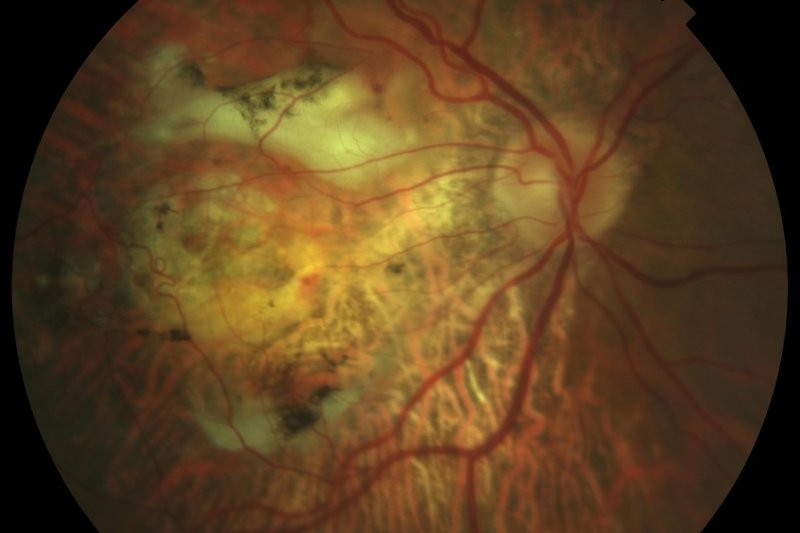

The majority of fungal CLMK infections are caused by Fusarium, Aspergillus and Candida species2, with an insidious course similar to Acanthamoeba keratitis. Fungal species exhibit a diverse range of morphologies and a constellation of presentations can be seen, including the classic description of a poorly defined fluffy infiltrate edged with satellite lesions (Fig 2). Extensive and deeply buried hyphae pose special challenges as they are too large to be ingested by host immune cells and require deeply penetrating antifungal formulations. The main risk factor is ocular trauma involving organic matter6 and thus a history of trauma should be documented. Thankfully, New Zealand has relatively low rates of fungal keratitis, with 2-5% positive on corneal scrapes3, 7.

Fig 2. Fusarium keratitis with ill-defined infiltrate, satellite lesions and hypopyon